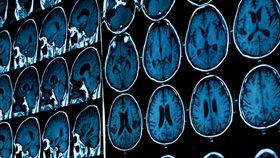

“The scan of the girl’s brain showed more than a hundred white dots, formed due to tapeworm eggs," Dr Praveen Gupta, director of the Artemis Hospital’s neurology department, told the Times of India. "Such an infection is caused by accidentally eating foods infested by tapeworms. When eggs reach the brain through the nervous system, they cause neurocysticercosis, which is characterised by a severe headache, epileptic seizures, and confusion."